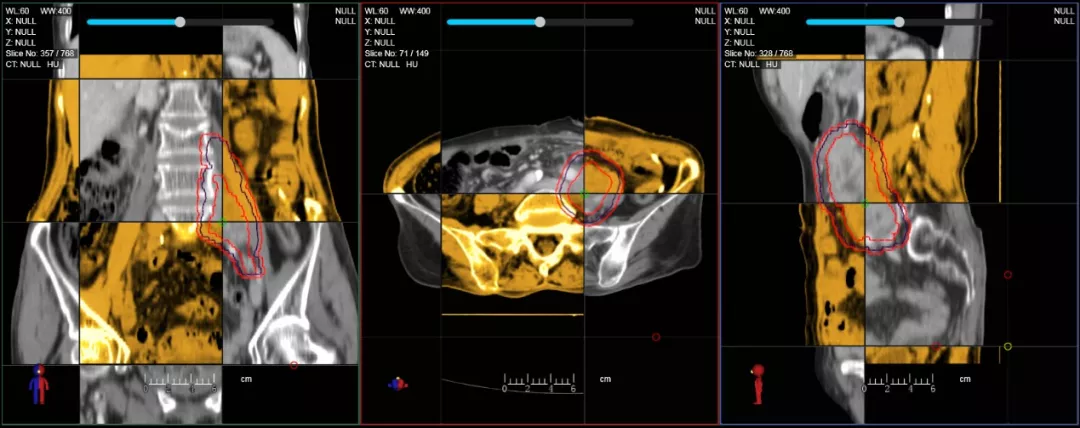

個(gè)體化自適應(yīng)放療

一體化CT-linac讓自適應(yīng)放療ART概念變?yōu)楝F(xiàn)實(shí)?;颊呷煶虪顟B(tài)監(jiān)控,適時(shí)在線調(diào)整治療計(jì)劃,精準(zhǔn)控制治療劑量,為患者動(dòng)態(tài)定制個(gè)體化治療方案。uAI賦能智能勾畫(huà)和自動(dòng)計(jì)劃,秒級(jí)勾勒靶區(qū)和危及器官,大幅縮短自適應(yīng)放療時(shí)間。

在線自適應(yīng)放療流程示意圖